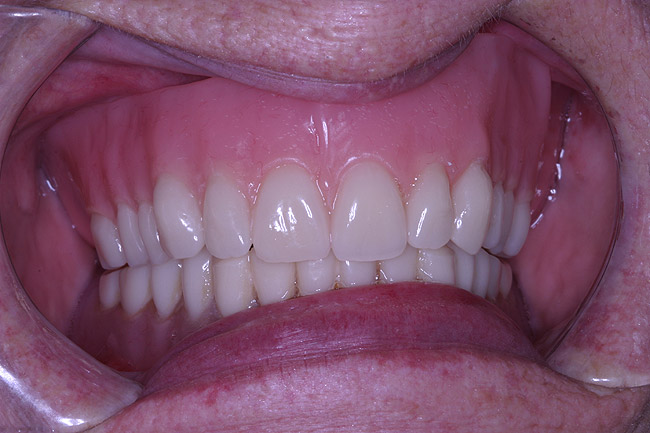

A 74-year-old woman presented with a chief complaint of a worn, stained,ill-fitting maxillary complete denture that she felt had minimal esthetic value (Figure 1). The optimal treatment plan consisted of a new, complete set of removable dentures but was not accepted by the patient due to financial constraints. The patient opted for a new maxillary denture with plans to replace the mandibular prosthesis at a later time.

Figure 1  Preoperative photograph of existing upper and lower dentures. Only the upper was to be fabricated.

Figure 1